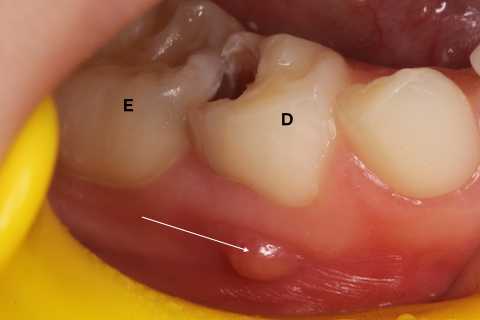

5歳男子、右下D、Per。右下E、隣接面カリエスPerというと歯髄が細菌感染していて炎症が歯根の外に波及し、腫れている。当然、神経は失活して(死んで)いるということになっているが、そうでもない。特に乳歯はそうでもなく、神経は完全には死んでいない。根管治療は全く必要ないことが多い。この症例も冠部歯髄を開けることもなく、3MI◯+α-TCPセメントで覆罩してCRで再建したが、特に問題なく治ると思う。そもそも神経を取るとか必要があるのか?とつくづく考えさせられる。5歳児を簀巻きにして押さえつけて麻酔をして処置をするとか、考えただけでも恐ろしい。生涯PTSDに悩まされるかもしれない。では時系列でどうぞ